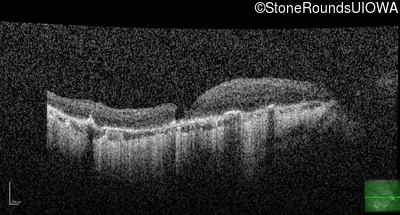

This 81 year old man began using a flashlight to read menus in his 40's. At age 75 his ophthalmologist noticed abnormal fundus findings and referred him to a retina specialist.

Diagnosis & molecular findings

| Disease | Gene | Allele 1 variant(s) | Allele 2 variant(s) | Inheritance mode |

|---|---|---|---|---|

| Late Onset Retinal Dystrophy | C1QTNF5 | Ser163Arg AGC>AGA | AD |

Disease:

Gene:

Allele 1:

Ser163Arg AGC>AGA

Allele 2:

Inheritance:

AD